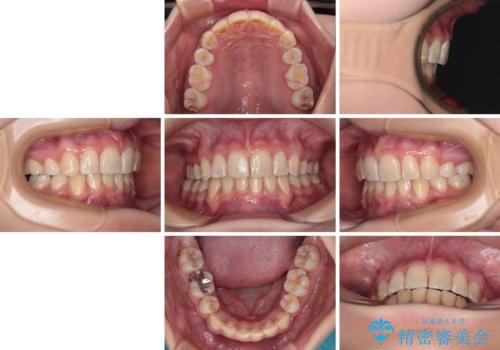

【モニター】出っ歯と八重歯 抜歯矯正でスッキリとした口元に

抜歯矯正により、口元の印象だけでなく、横顔の印象も大きく改善されました。